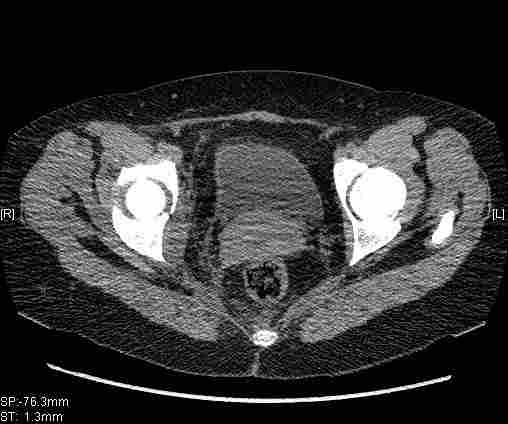

Удалось сегодня вывести пациентку в соседнюю больницу, где есть кт. Срезы сделаны только горизонтальные.